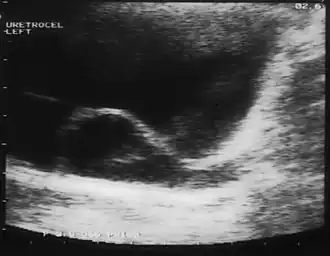

El diagnóstico puede establecerse por ecografía de todo el tracto urinario (técnica de diagnóstico por imágenes que utiliza ondas de sonido de alta frecuencia, que tras atravesar tejidos de diferente densidad, son computabilizadas, dando una imagen de los vasos sanguíneos, tejidos, órganos internos, colecciones de líquido, masas, etc.). En ocasiones debe realizarse una pielografía endovenosa (PEV) que es una técnica diagnóstica radiológica en la que se administra un contraste endovenoso, que durante su excreción por la vía urinaria permite visualizar mediante radiografías seriadas, la velocidad y trayectoria del flujo urinario. También permite detectar alteraciones morfológicas congénitas (duplicidad pielocalicilar) o patológicas (hidronefrosis, obstrucciones intrínsecas y extrínsecas, etc.). UROGRAMA ESCRETOR,CISTOURETEROGRAFIA MICCIONAL EN PACIENTES ADULTOS

Imagen de ureterocele: [1]